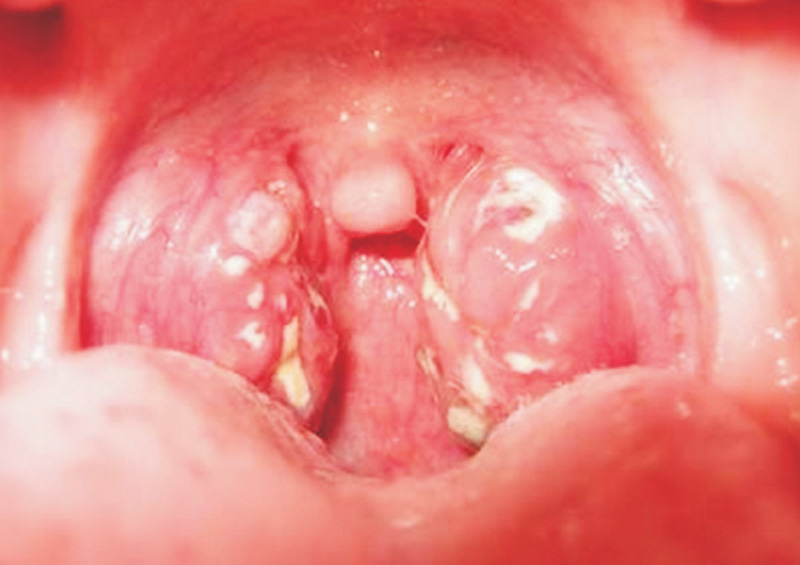

- Sau 2-3 ngà !important;y thì xuất hiện giả mạc ở mặt sau hoặc 2 bên thành họng, có màu trắng ngà, xám hoặc đen. Đây là dấu hiệu quan trọng để phát hiện bệnh. Nó làm cho bệnh nhân khó thở, khó nuốt.